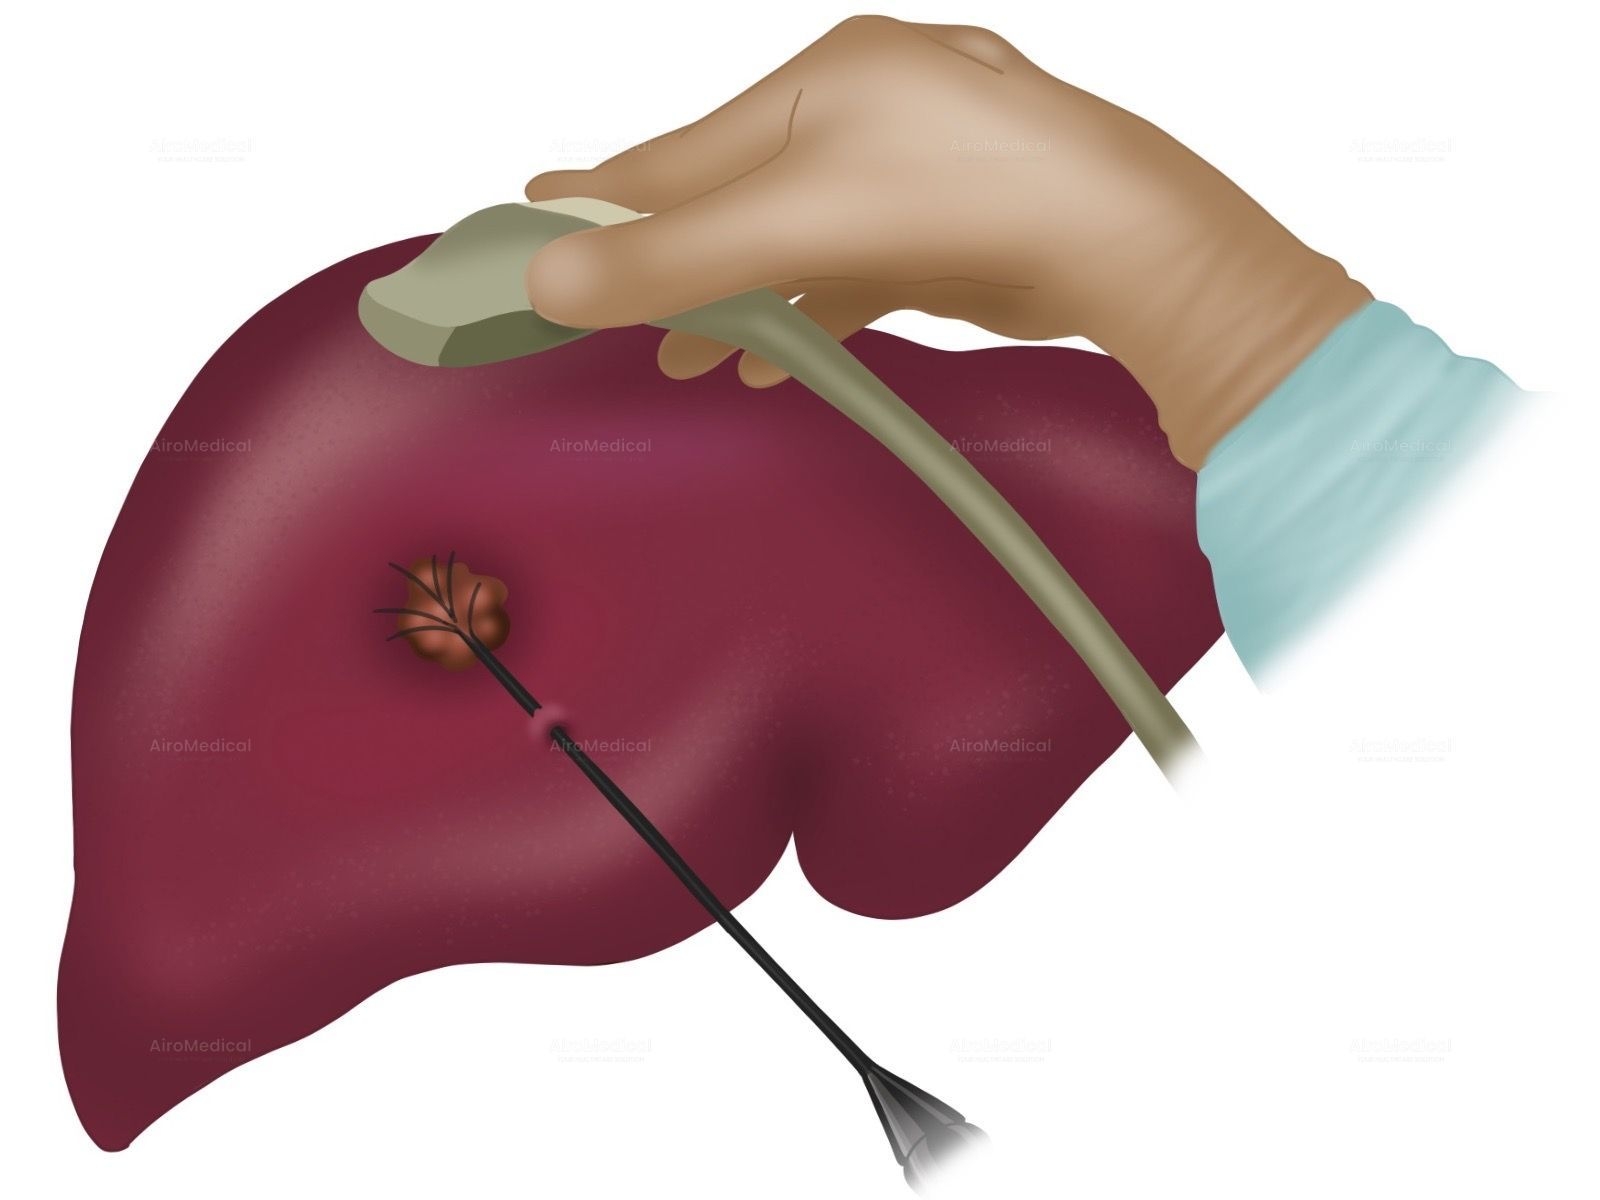

Is University Hospital Frankfurt suitable for patients with cancer?

It is one of the largest institutions dealing with cancer treatment. The oncology unit has a spiral tomograph, a gamma knife, PET, and other latest-generation equipment. Moreover, the team has performed hundreds of successful operations to treat the most complex oncological diseases.